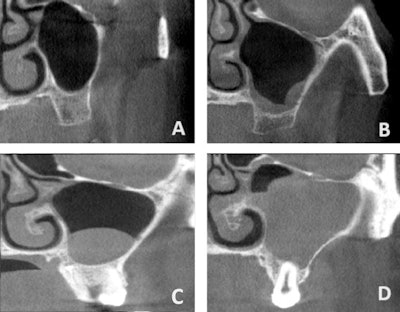

Sinus pathologies were found in 39.5% of sinuses and affected 54.8% of patients. Mucosal thickening was the most common condition (61%) followed by cysts or polyps (27.6%) and opacifications (11.4%). Men had a significantly higher rate of cysts and polyps (p = 0.020), while mucosal thickening did not vary by gender, Küçükkurt wrote.

Maxillary sinus conditions identified via CBCT. (A) Clear sinus, (B) mucosal thickening, (C) cyst/polyp, (D) opacification (≥ 50% of sinus volume). Images and captions courtesy of Küçükkurt. Licensed under CC BY-NC-ND 4.0.

Furthermore, odontogenic factors were present in 65.2% of affected sinuses, especially in mucosal thickening cases, with periapical lesions, both untreated and treated with RCT, strongly linked to pathology (p < 0.0001 and p = 0.013), unlike RCT teeth without lesions (p = 0.411). Complete sinus opacification occurred in 5% of cases, and patients ages 41 to 60 had a significantly higher rate of bilateral sinus involvement (p < 0.0001). Mucosal thickening was more often bilateral, while cysts were typically unilateral (p = 0.003).